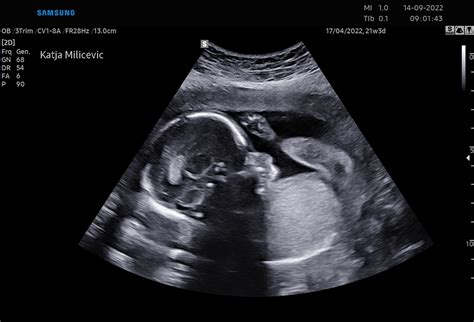

V 35. tednu nosečnosti je dojenček že skoraj popolnoma razvit in ga lahko primerjamo z velikostjo ananasa. Tehta približno 2400 gramov in meri okoli 46,5 cm. Čeprav se njegova rast v dolžino ne bo več tako drastično nadaljevala, bo v preostalih tednih še pridobil približno kilogram telesne teže. Podkožno maščevje se še naprej prerazporeja, kar pomaga koži postati manj nagubana in bolj gladka.

Ključnega pomena je, da se v tem obdobju nadaljuje razvoj dojenčkovih organov, zlasti pljuč, ki še vedno dozorevajo. Njihova pripravljenost bo ključna za samostojno dihanje po rojstvu. Otrokov imunski sistem zdaj deluje neodvisno od materinega krvnega obtoka. Dojenček je že absorbiral vsa potrebna protitelesa za razvoj svoje odpornosti in bo po rojstvu tako zaščiten pred tipičnimi okoljskimi tveganji. Vendar pa njegov imunski sistem še ni povsem razvit - telo bo potrebovalo še nekaj let, da bo popolnoma imuno, zato so dojenčki in majhni otroci še posebej ranljivi za patogene.

Medtem ko se otrok pripravlja na zunanji svet, se koordinacija njegovih gibov izboljšuje, čeprav za intenzivnejše premikanje nima več veliko prostora. Nadaljuje z razvojem svojih refleksov; če zazna svetlobo, se obrne proti njej. Prebavni organi, kot so ledvice in jetra, že opravljajo svoje naloge. Ledvici odstranjujeta odpadne produkte presnove preko urina, jetra pa shranjujejo beljakovine in vitamine ter pretvarjajo sladkor v glukozo za krvni obtok. V otrokovem črevesju se začne tvoriti mekonij, temnozelena ali črna snov, ki jo bo izločil po rojstvu. Mekonij je sestavljen iz zaužite plodovnice, voskaste snovi (vernix caseosa), dlačic lanugo in gostega žolča.

Sluh dojenčka je v 35. tednu že popolnoma razvit in se najbolje odziva na visoke tone. To je čas, ko lahko bodoča mamica že občuti močnejše brce in premikanje, ki pa so občasno omejena zaradi vse manjšega prostora v maternici.